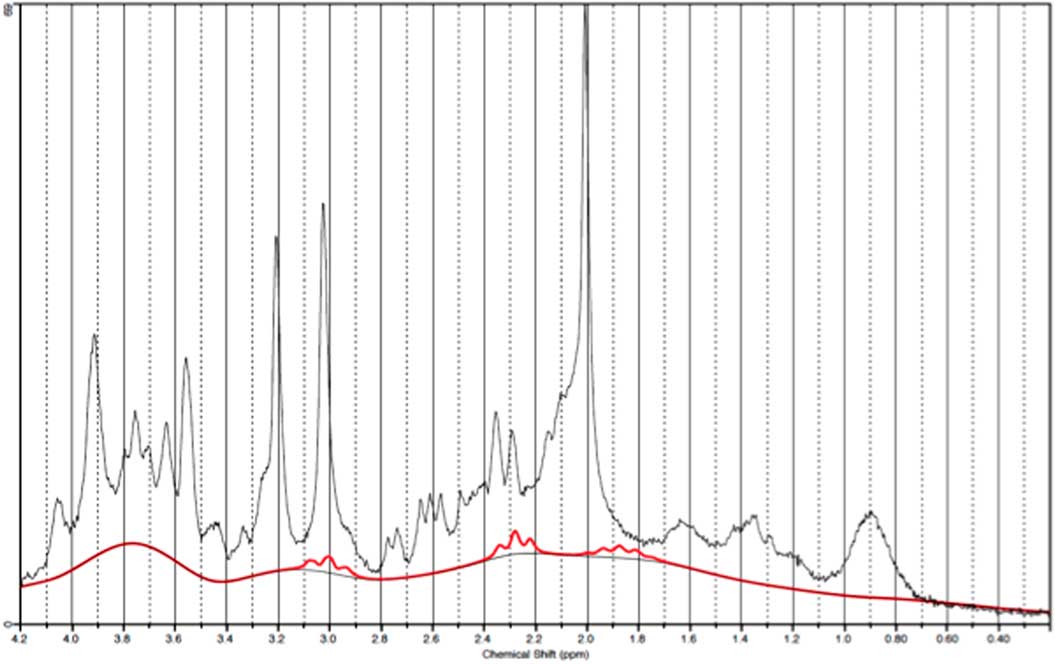

GABA measurements in OCC

Data from one occipital follow-up scan was discarded due to poor spectral quality. Figure 6 illustrates a representative spectra from OCC and Fig. 7 an individual plot for the GABA signal in OCC. When performing direct comparison between patients at baseline and healthy subjects, we found no significant difference in GABA/Cr ratios t(21)=0.37, p=0.72. The same applied when comparing pre- and post-ECT GABA/Cr levels in patients t (20)=0.78, p=0.47. Moreover, no significant correlation was found between pre-ECT GABA/Cr levels and HAM-D17 ratings (p=0404).

Fig. 6 Example of a representative spectrum from the occipital cortex. The raw data are plotted as a thin black curve. The thick red curve is the LcModel fit to this data. The baseline is also plotted as a thin black curve. At the top are plotted the residuals.

Fig. 7 Example of an individual plot for γ-aminobutyric acid from the occipital cortex. The raw data are plotted as a thin black curve. The thick red curve is the LcModel fit to this data.